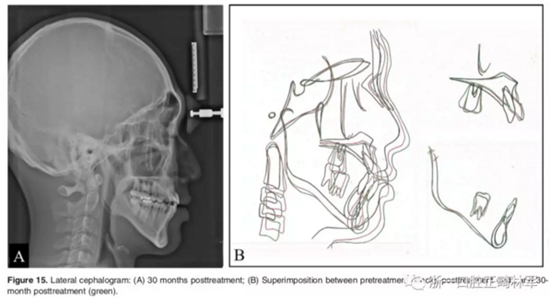

影像學(xué):頭顱側(cè)位片示:矢狀向和垂直向骨骼發(fā)生變化(ANB角,3°;SN-MP,51°);上頜切牙略前傾(U1-SN,106°),與下頜切牙一致(IMPA,75°);病人的面部輪廓得以保持。全景片示:由于牙齒萌出,上前牙區(qū)垂直向牙槽骨水平增加;雖然前牙牙根較彎曲,但其平行度仍可,且無(wú)明顯的牙根吸收。CBCT示:前牙唇側(cè)骨質(zhì)連續(xù)性改善,牙根唇側(cè)支持組織變好,牙槽骨高度、厚度均有增加,但轉(zhuǎn)矩的改變一定程度上導(dǎo)致了局部應(yīng)力的增大。

2年隨訪:咬合關(guān)系保持穩(wěn)定,無(wú)明顯復(fù)發(fā),下頜有一定晚期生長(zhǎng)趨勢(shì);前牙牙齦外形、牙冠高度無(wú)明顯變化;唇側(cè)牙槽骨高度、厚度均保持良好。